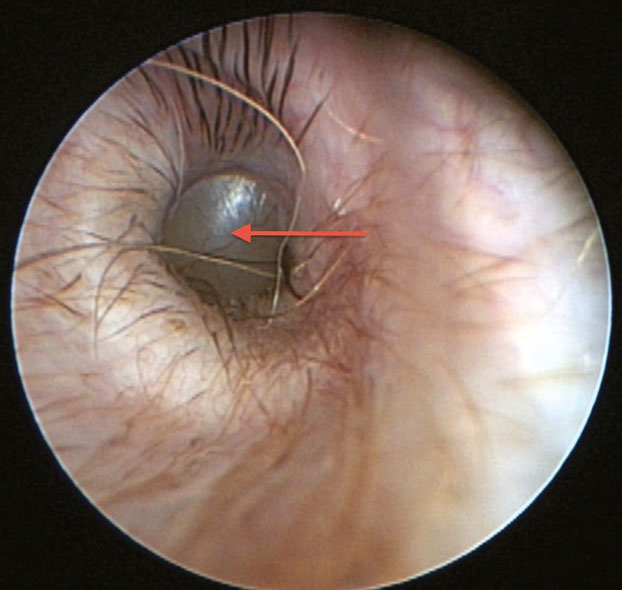

• video-otoscope

A more sophisticated form of otoscopy is video-otoscopy. It uses a

high-powered, fiber-optic camera which enables in-depth views of the two

sections of the canal -- vertical and horizontal -- and the eardrum.

General anesthesia is required for this procedure. It is combined with a

port that enables flushing and suction of the

canal,

to remove wax, mucous, and debris. This is necessary to thoroughly clean

the canal for best visualization of the eardrum.

canal,

to remove wax, mucous, and debris. This is necessary to thoroughly clean

the canal for best visualization of the eardrum.

In this video-otoscopic image at the left, of the left ear canal and tympanic membrane of a cavalier, the red arrow points to a large, bulging pars flaccida. (Photo from Dr. Lynette Cole's December 2015 report.) However, cavaliers may have PSOM even though their pars flaccida is flat rather than bulging.

Video-otoscopy also is used in preparation of and during the surgical procedure, myringotomy, described below.